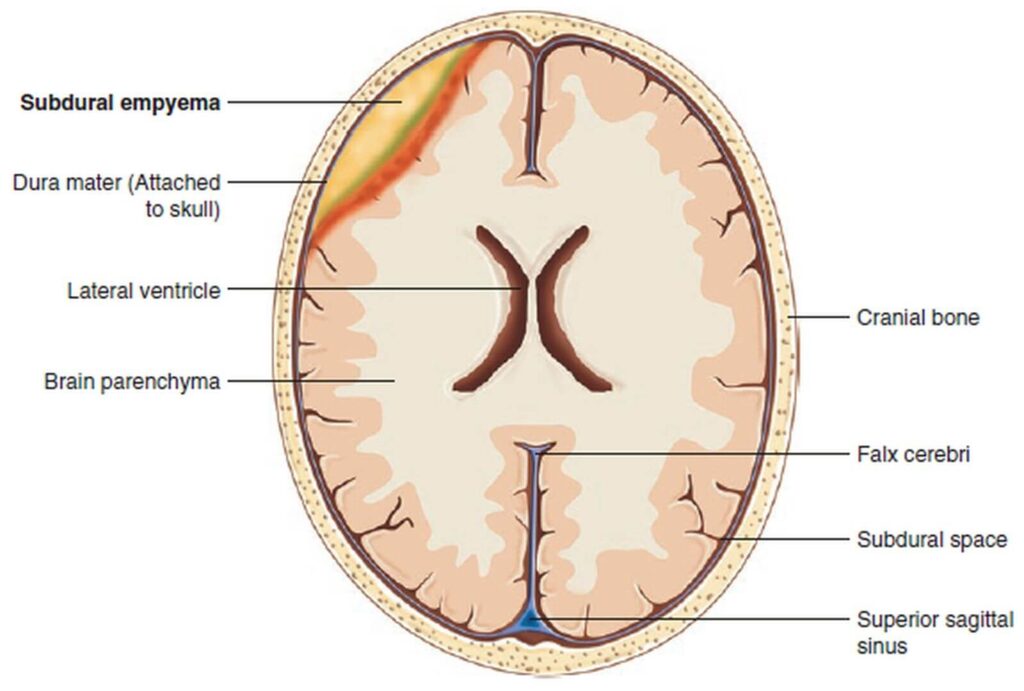

A concussion is an injury that is accompanied by damage to brain tissue, swelling, and sometimes hemorrhage.

- MRI or CT scan to detect damage and swelling

- Surgery in case of severe bleeding or swelling